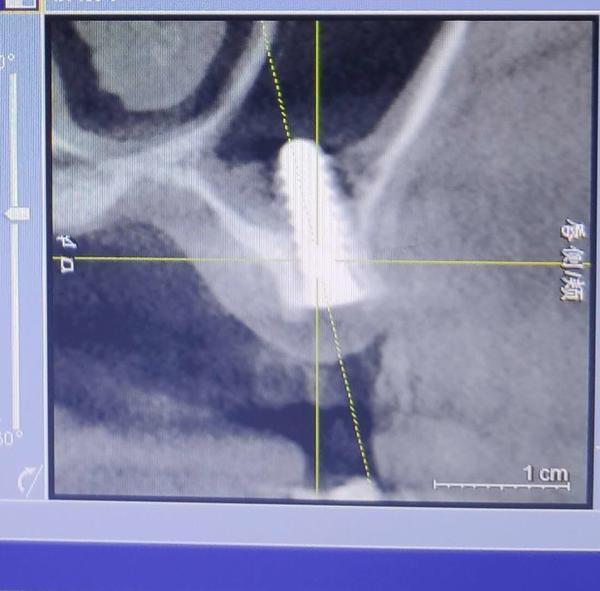

2019年下半年,在出現(xiàn)了不適反應(yīng)后,葉女士到沈陽一家部隊醫(yī)院口腔門診求醫(yī)。經(jīng)CT等檢查,她才發(fā)現(xiàn),原來有一顆種植體已經(jīng)進(jìn)入了她的上頜竇腔。

葉女士做出的影像檢查結(jié)果顯示,其中一顆植體已經(jīng)進(jìn)入上頜竇腔內(nèi)。

2019年7月,在出具的診斷證明上,沈陽市當(dāng)?shù)匾患胰揍t(yī)院的知名口腔診療專家說,該種植體已經(jīng)進(jìn)入上頜竇腔,需要取出。